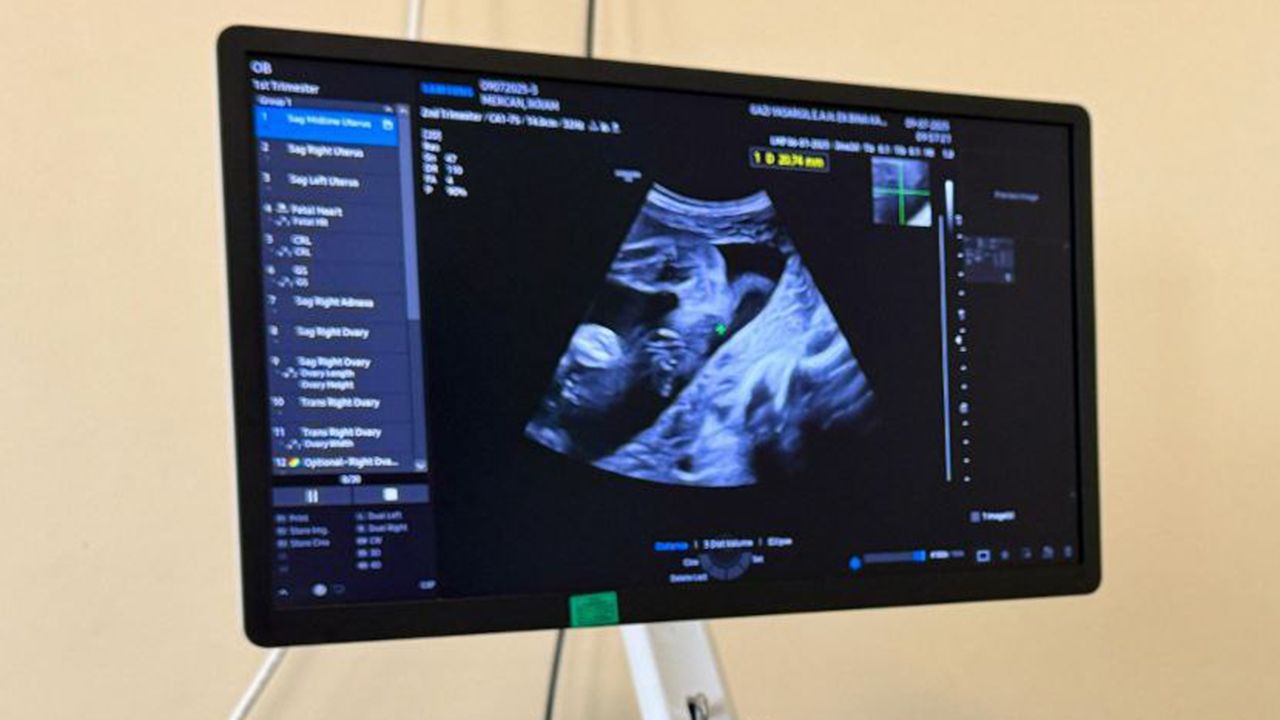

Göreve başlayan Perinatoloji Uzmanı Doç. Dr. Derya Uyan Handem, yüksek riskli gebeliklerin tanı ve tedavisinde aktif rol üstlenecek.

Handem, perinatolojinin, gebelik sürecinde ortaya çıkabilecek sağlık risklerinin erken teşhisi ve yönetiminde kritik bir branş olduğunu vurguladı.

Perinatoloji, kadın hastalıkları ve doğum uzmanlığının bir yan dalı olup; yüksek riskli gebeliklerin izlenmesi, tanısı ve tedavisiyle ilgilenir. Normal gebelikler kadın doğum uzmanlarınca takip edilirken, riskli durumlar perinatoloji uzmanlarının kontrolünde yürütülür.